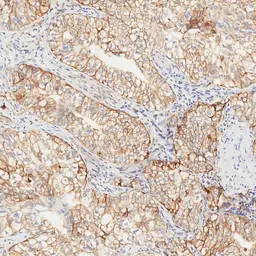

Anti-PD-L1 antibody [H302] HistoMAX&trade; used in IHC (Paraffin sections) (IHC-P). GTX639925

GTX639925 IHC-P Image

IHC-P analysis of human esophageal adenocarcinoma (EAC) tissue using GTX639925 PD-L1 antibody [H302] HistoMAX™.

PD-L1 negative esophageal adenocarcinoma showing intense PD-L1 positivity of tumor adjacent macrophages.